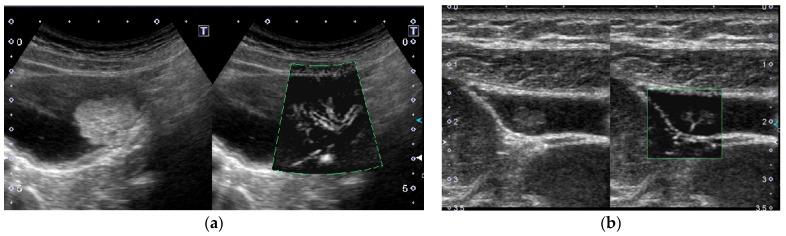

The most important role of ultrasound (US) in the management of gallbladder (GB) lesions is to detect lesions earlier and differentiate them from GB carcinoma (GBC). To avoid overlooking lesions, postural changes and high-frequency transducers with magnified images should be employed. GB lesions are divided into polypoid lesions (GPLs) and wall thickening (GWT). For GPLs, classification into pedunculated and sessile types should be done first. This classification is useful not only for the differential diagnosis but also for the depth diagnosis, as pedunculated carcinomas are confined to the mucosa. Both rapid GB wall blood flow (GWBF) and the irregularity of color signal patterns on Doppler imaging, and heterogeneous enhancement in the venous phase on contrast-enhanced ultrasound (CEUS) suggest GBC. Since GWT occurs in various conditions, subdividing into diffuse and focal forms is important. Unlike diffuse GWT, focal GWT is specific for GB and has a higher incidence of GBC. The discontinuity and irregularity of the innermost hyperechoic layer and irregular or disrupted GB wall layer structure suggest GBC. Rapid GWBF is also useful for the diagnosis of wall-thickened type GBC and pancreaticobiliary maljunction. Detailed B-mode evaluation using high-frequency transducers, combined with Doppler imaging and CEUS, enables a more accurate diagnosis.

超声(US)在胆囊(GB)病变管理中的最重要作用是更早地检测病变并将其与胆囊癌(GBC)区分开来。为避免漏诊病变,应采用体位改变以及具有放大图像的高频探头。GB病变分为息肉样病变(GPLs)和胆囊壁增厚(GWT)。对于GPLs,应首先分为有蒂型和无蒂型。这种分类不仅有助于鉴别诊断,也有助于深度诊断,因为有蒂癌局限于黏膜层。胆囊壁血流(GWBF)快速、多普勒成像时彩色信号模式不规则以及对比增强超声(CEUS)静脉期不均匀强化均提示GBC。由于GWT可在多种情况下出现,将其细分为弥漫性和局灶性形式很重要。与弥漫性GWT不同,局灶性GWT是GB特有的,且GBC发生率更高。最内层高回声层的连续性中断和不规则以及GB壁层结构不规则或破坏提示GBC。快速GWBF对壁增厚型GBC和胰胆管汇合异常的诊断也有帮助。使用高频探头进行详细的B超评估,结合多普勒成像和CEUS,可实现更准确的诊断。